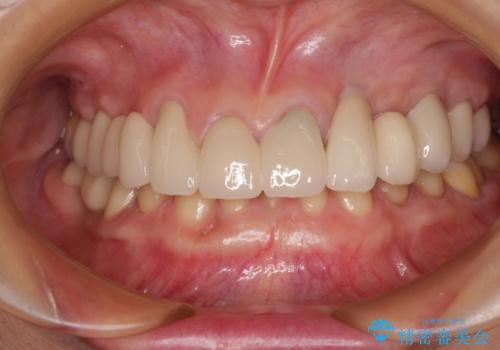

[ 金属アレルギー ] 銀歯を除去するメタルフリー治療

担当医 大元洋佑

![[ 金属アレルギー ] 銀歯を除去するメタルフリー治療の症例 治療後](https://seimitsushinbi.jp/wp/wp-content/uploads/2023/08/285add314246a78e4e98332cd6f9956a-500x350.jpg?v=1692755948)